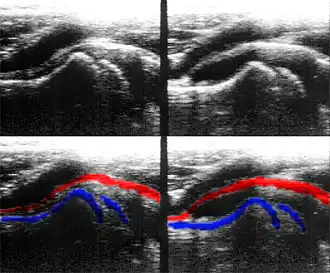

Bei der eitrigen Arthritis kommt es zu einer ausgeprägten Entzündungsreaktion mit Rötung, Schwellung und Überwärmung, wenn die Gelenke oberflächlich liegen (Knie, Ellenbogen, Sprunggelenk). Hinzu treten erhebliche Schmerzen, die durch Bewegung intensiviert werden. Belastung und Bewegung im betroffenen Gelenk sind eingeschränkt. Bei Kindern besteht eine Spielunlust. Das betroffene Gelenk wird spontan nicht mehr belastet oder bewegt. Meist kommt es auch zu einer allgemeinen Krankheitssymptomatik. Diagnostisch zeigt sich ein Gelenkerguss, der z. B. an Knie und Ellenbogen tastbar, an den anderen Gelenken, z. B. an der Hüfte, sonografisch darstellbar ist. Bei der Blutuntersuchung finden sich erhöhte Entzündungswerte (C-reaktives Protein, Leukozytenzahl, Blutsenkungsgeschwindigkeit). Bei klinischem Verdacht auf eine eitrige Arthritis sollte eine umgehende Gelenkpunktion erfolgen. Das Aussehen des Gelenkergusses dient der weiteren Differenzierung. Auch kann ein Abstrich entnommen werden und daraus ein Erregernachweis erfolgen.